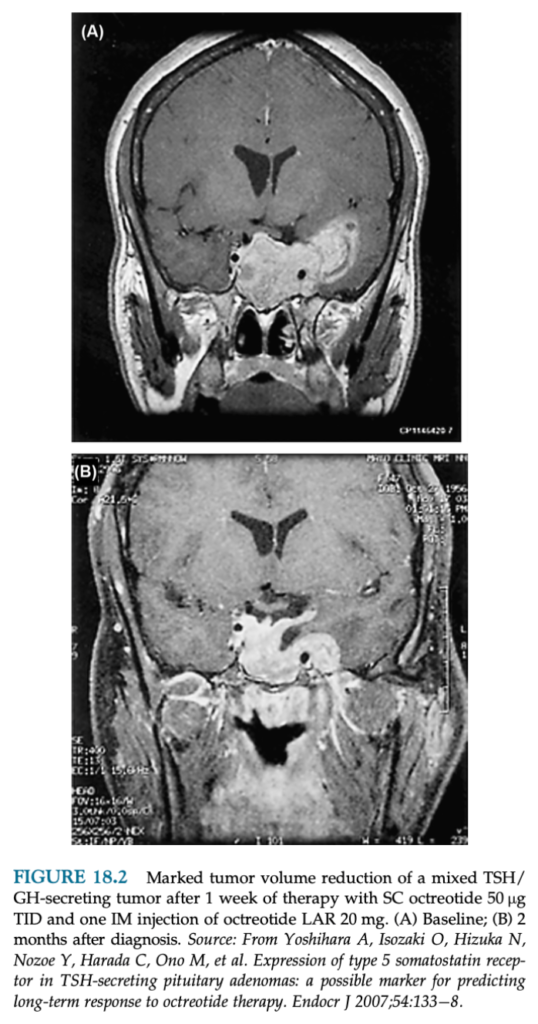

TSH産生下垂体腺腫はSSTR-2,5を発現していてソマトスタチンアナログによりTSH分泌が減少し、腫瘍も縮小する。

ソマトスタチンアナログの短期間(2週間)の投与で、90%の患者でTSHが平均74% 減少して、73%の患者で甲状腺ホルモンが正常となる。

治療を継続すると84-95%が甲状腺ホルモンが正常になり、40-50%に腫瘍の縮小を認める。

甲状腺腫大が20%の患者で改善。視野の改善を75%に認める。